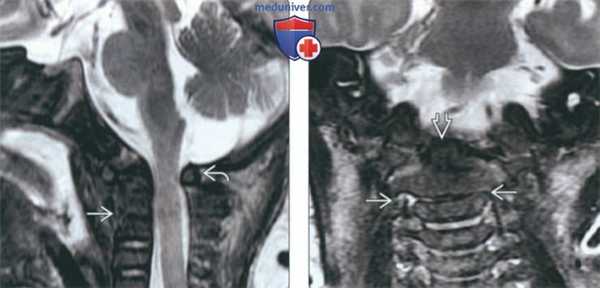

(Слева) На сагиттальной МРТ (Т2 ВИ) визуализируется маленький рудиментарный межпозвонковый диск на уровне С2-С3 (врожденное нарушение сегментации). Также определяется тяжелый стеноз позвоночного канала вследствие гипоплазии дуги С1.

(Справа) На корональной MPT (Т2 ВИ) у ребенка с врожденным нарушением сегментации С2-С3 определяется гипоплазия диспластического зубовидною отростка с наклоном его вправо. Слегка асимметричное поражение рудиментарною диска С2-С3 приводит к легкому сколиозу шейного отдела позвоночника.